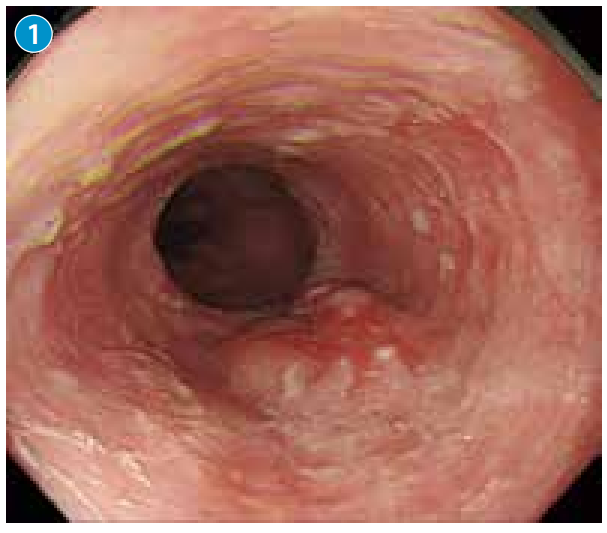

●背景黏膜血管透见性差,局部黏膜粗糙。在胸部下段食管后壁,见一中央伴有凹陷的平缓隆起性病变。

●通过减少空气量,观察病变,并没有发现病变形态改变,考虑病变整体较厚、较硬(→)。

●胸部下段食管单发臼齿状隆起,考虑颗粒细胞瘤的可能。

图片右侧为口侧。在黏膜平缓隆起的中央,观察到不规则的发红凹陷。